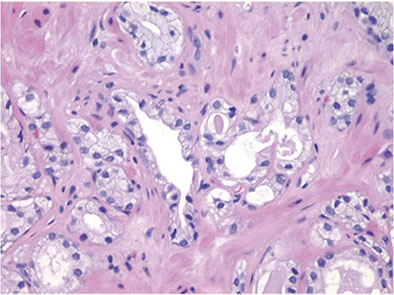

Foamy glands ca can be seen c abundant foamy cytoplasm, c gland crowding or infiltrative glands, usually c pink acellular intraluminal secretions

- though cytoplasm can appear xanthomatous, it does  not contain lipid, but empty vacuoles

- nuclear enlargement and prominent nucleoli usually absent

- nuclei are usually small, round and hyperchromatic

- foamy gland ca usually admixed c regular prostatic AC

- can have prominent desmoplastic stromal rxn, which can obscure the ca

- occasional cells may aberrantly express HMWK in non-basal cells

Foamy gland AC